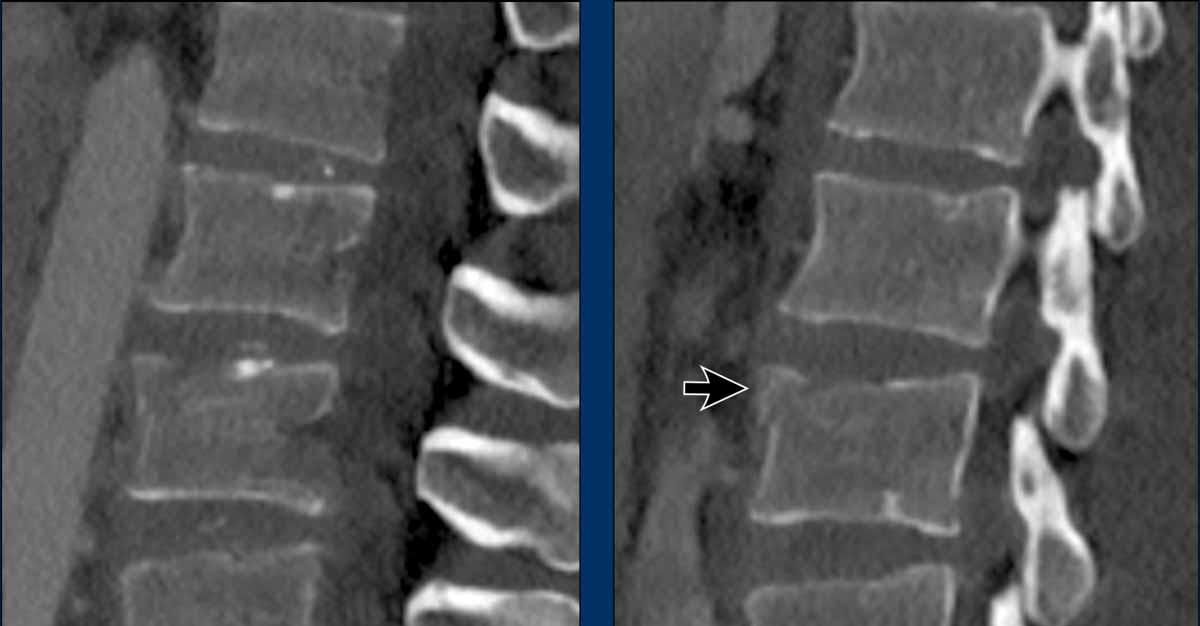

What is the AO-type of the vertebral body fracture based on only these two inages?

Findings:

- Fractures of the vertebral body with involvement of upper endplates (1 points) and posterior wall (2 points)

- Bulging of the posterior wall without any other signs of dislocation is the result of the burst fracture.

Therefore no C injury.

Conclusion

Injury type A3